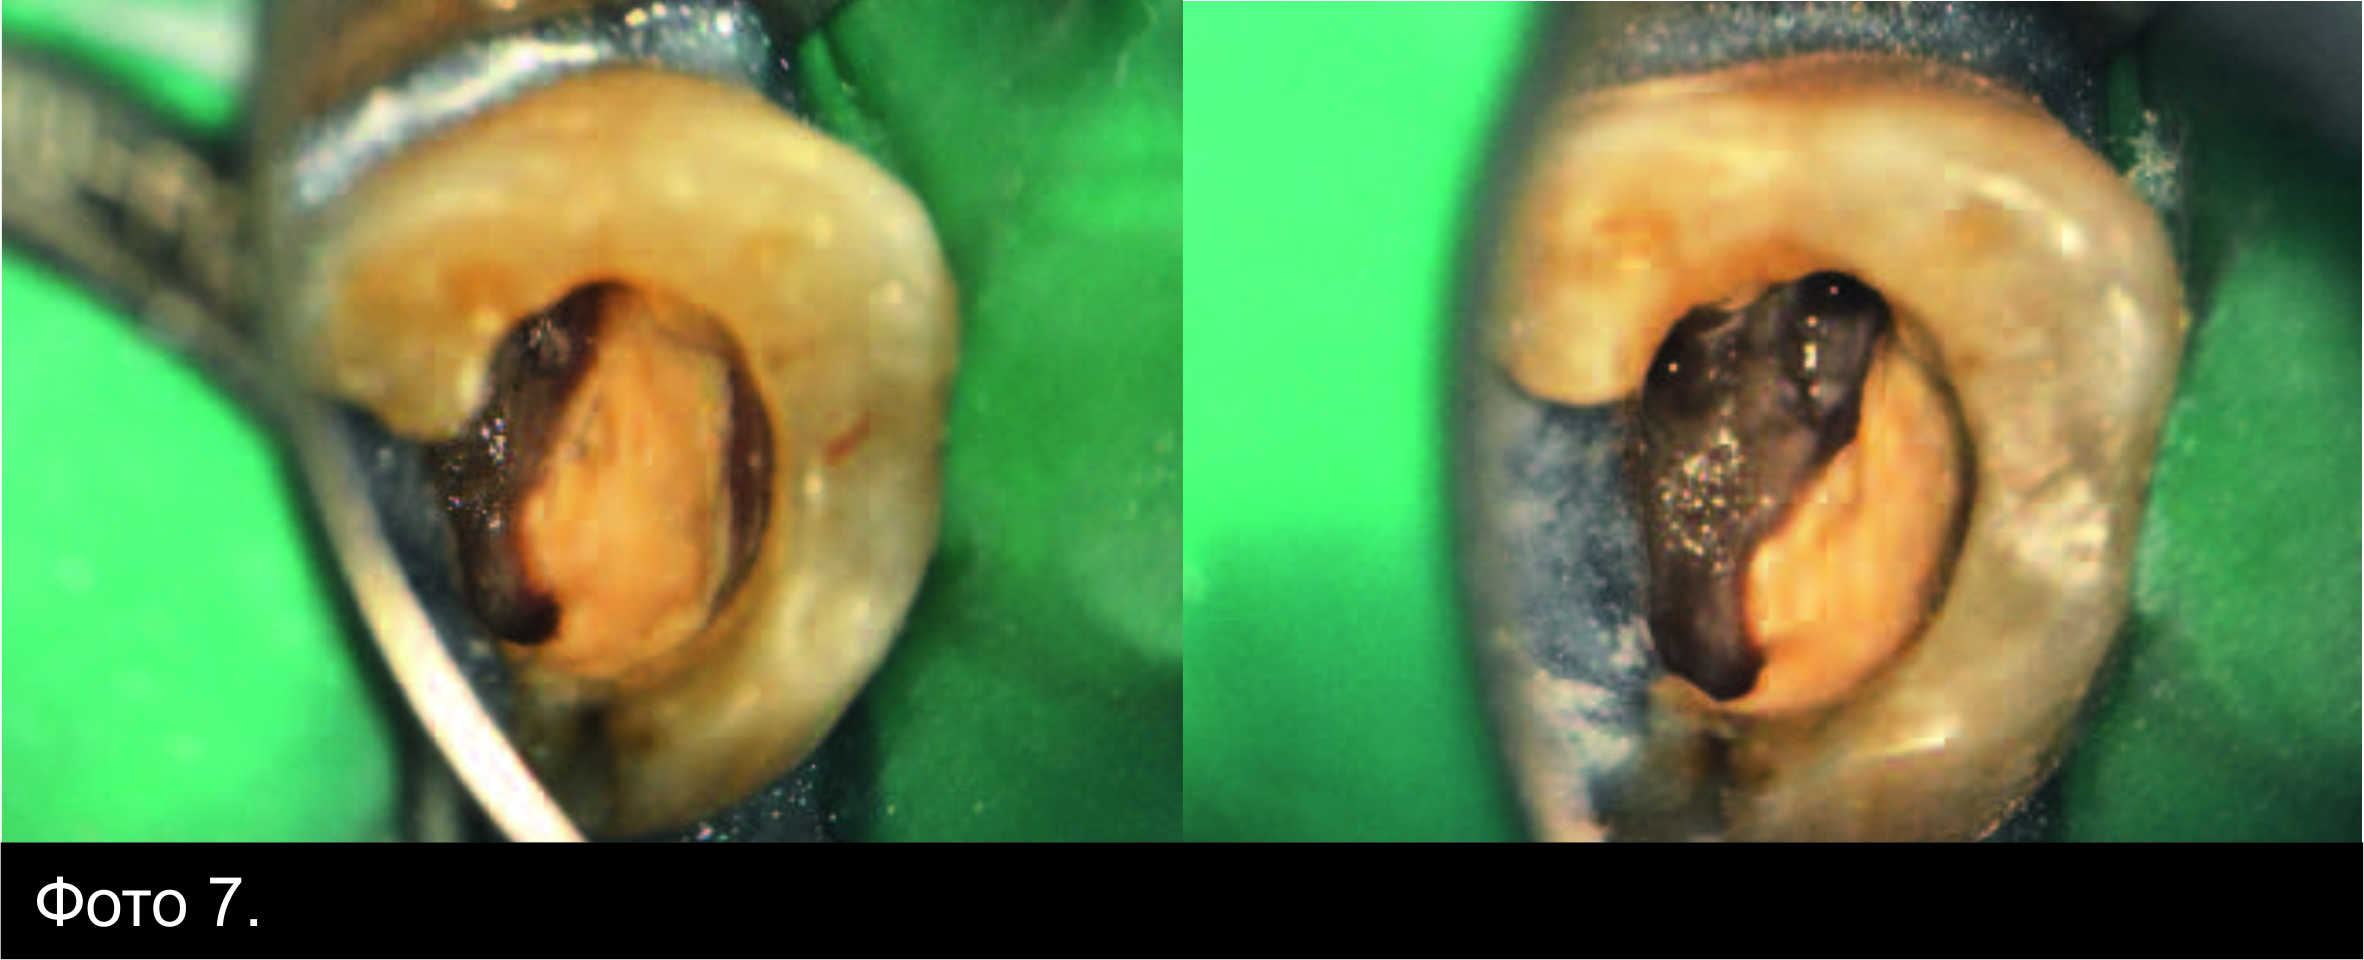

Фото 7. Зовнішній вигляд ділянки, загерметизованої

Biodentine™ під час другого відвідування.

Вдруге пацієнт прийшов із переломом

дистально-піднебінного бугра. Коли зуб ізолювали, а тимчасову пломбу видалили,

виявили, що Biodentine™ був твердим, і в ньому не було жодних змін (Фото 7). Завершальну іригацію виконали 5%